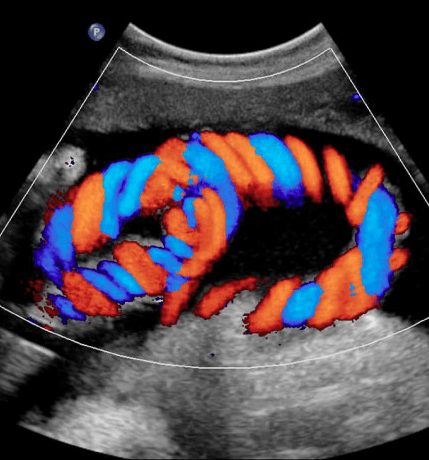

- Real-time blood flow insight: Color Doppler ultrasound shows blood movement within vessels and the heart, helping clinicians detect blockages, leaks, or abnormal flow patterns.

- Technology you can trust: Modern Doppler machines with high-resolution imaging improve diagnostic accuracy.

- Modern imaging suite: Equipped with up-to-date Doppler ultrasound machines designed to capture precise motion and flow.